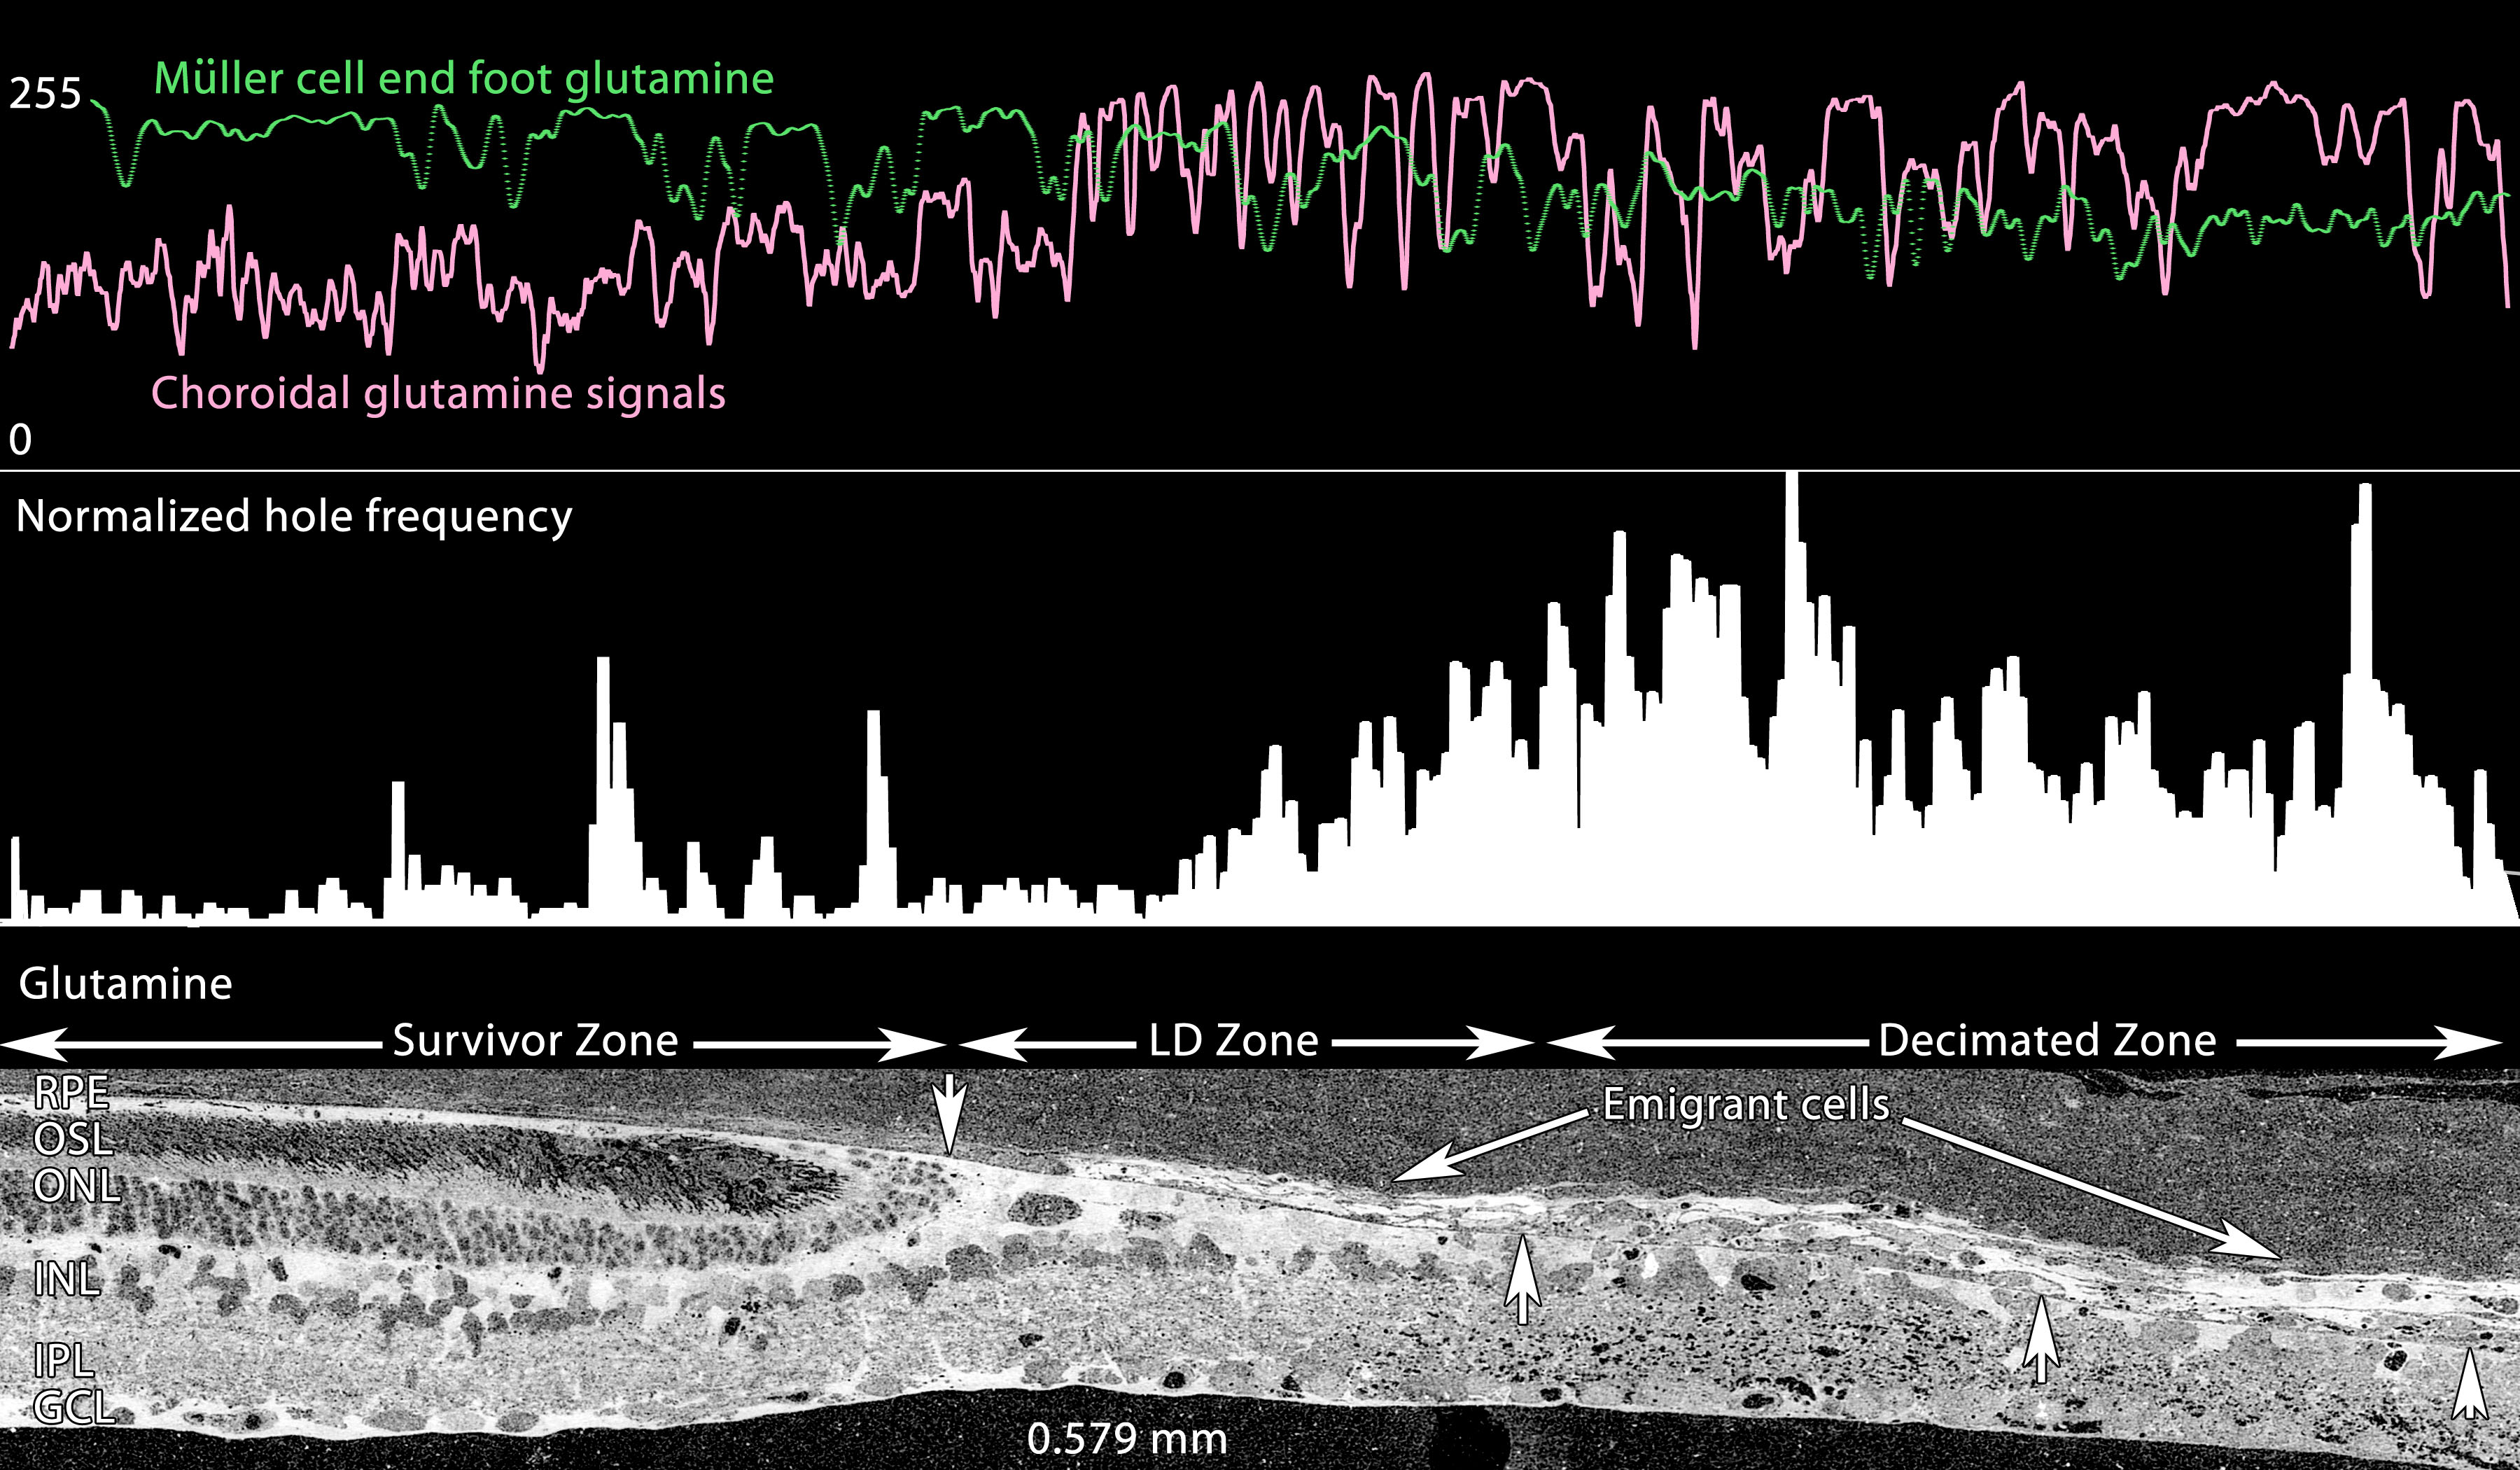

Figure 13. Glutamine profiles across the

Survivor-light damage (LD)-Decimation gradient. Visualization:

Quantitative gray-scale images of glutamine signals displayed as

intensity. Up arrows, remnant retina-choroid interface; downward arrow

is the small high glutamine seal region. The bottom panel is 0.579 mm

wide and shows isolated glutamine gradients in retina, retinal pigment

epithelium (RPE), choroid, seal, emigrant and decimated zones. All

decimated zones show large numbers of holes (see Methods). Sample

metadata: SD Rat, age at LX 60 d, animal #P240–2L-24, left eye, 24 h

LX, harvested at 240 days pLX, bloc code 6685, slide code 3518.